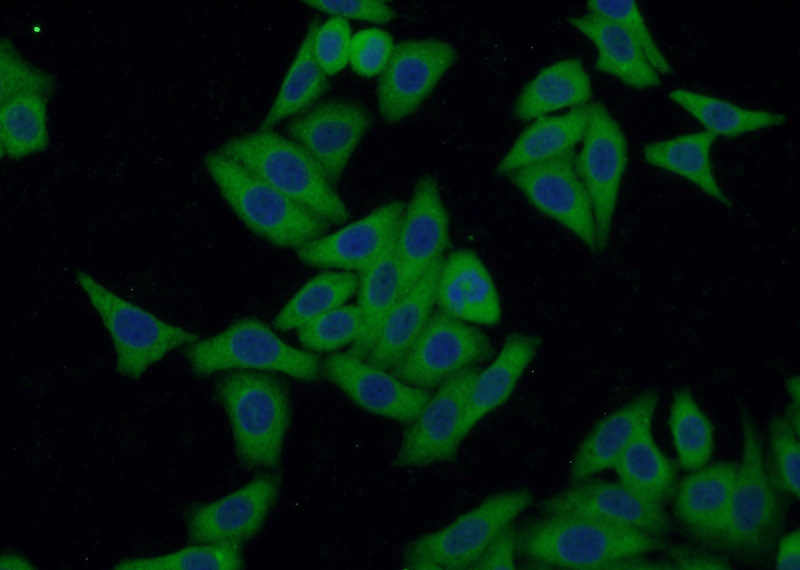

Immunofluorescent analysis of HepG2 cells using Catalog No:113553(P53 Antibody) at dilution of 1:50 and Alexa Fluor 488-congugated AffiniPure Goat Anti-Rabbit IgG(H+L)